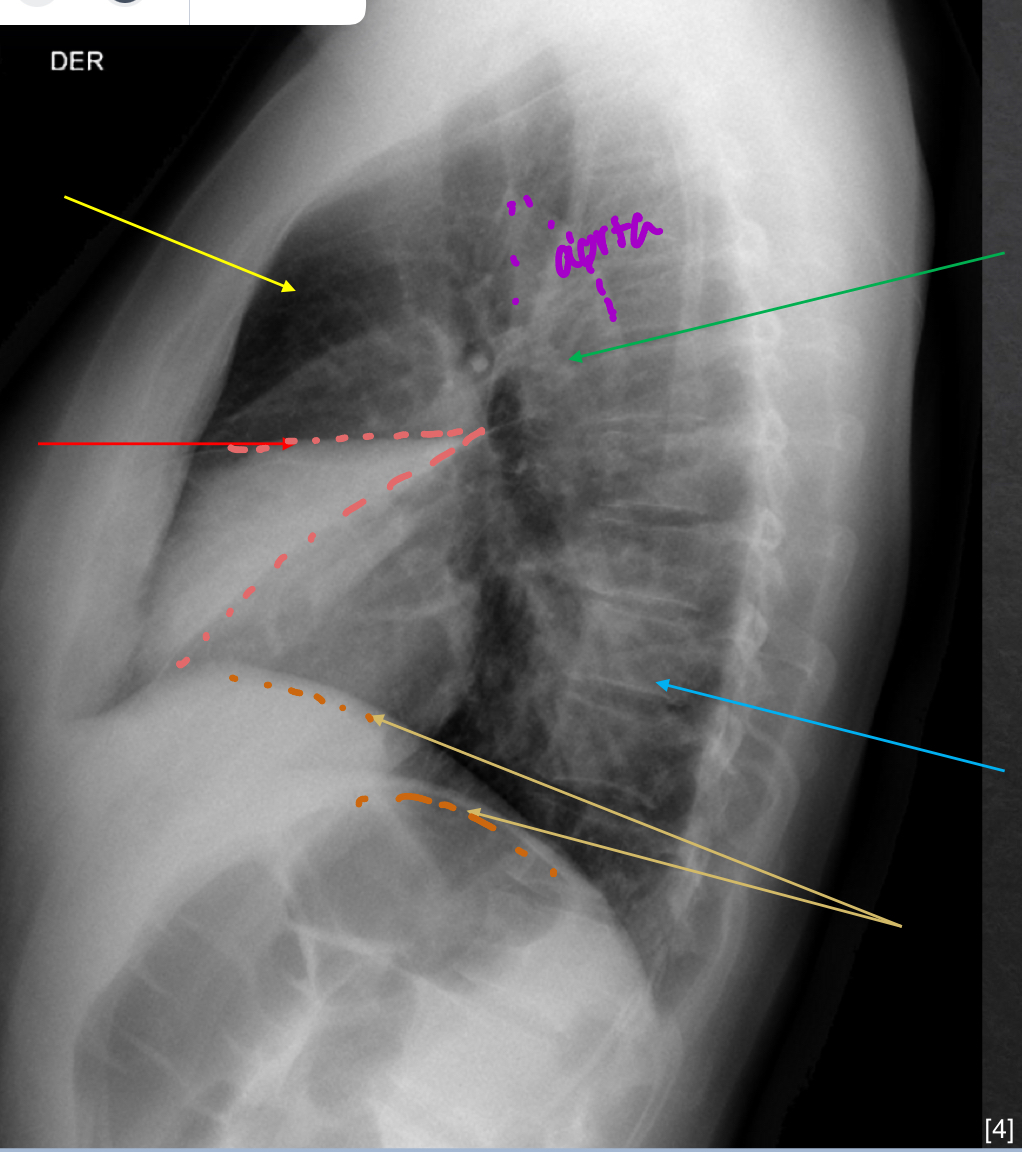

what to look for on lateral view xray

retrosternal space

hilar region

fissures

thoracic spine

diaphragm and posterior costophrenic sulci

yellow: retrosternal spcae-clear

green: hilar region- no mass

red: fissures- VISIBLE

blue: thoracic spine- good

orange: diaphram and post costo sulci- slightly elevated